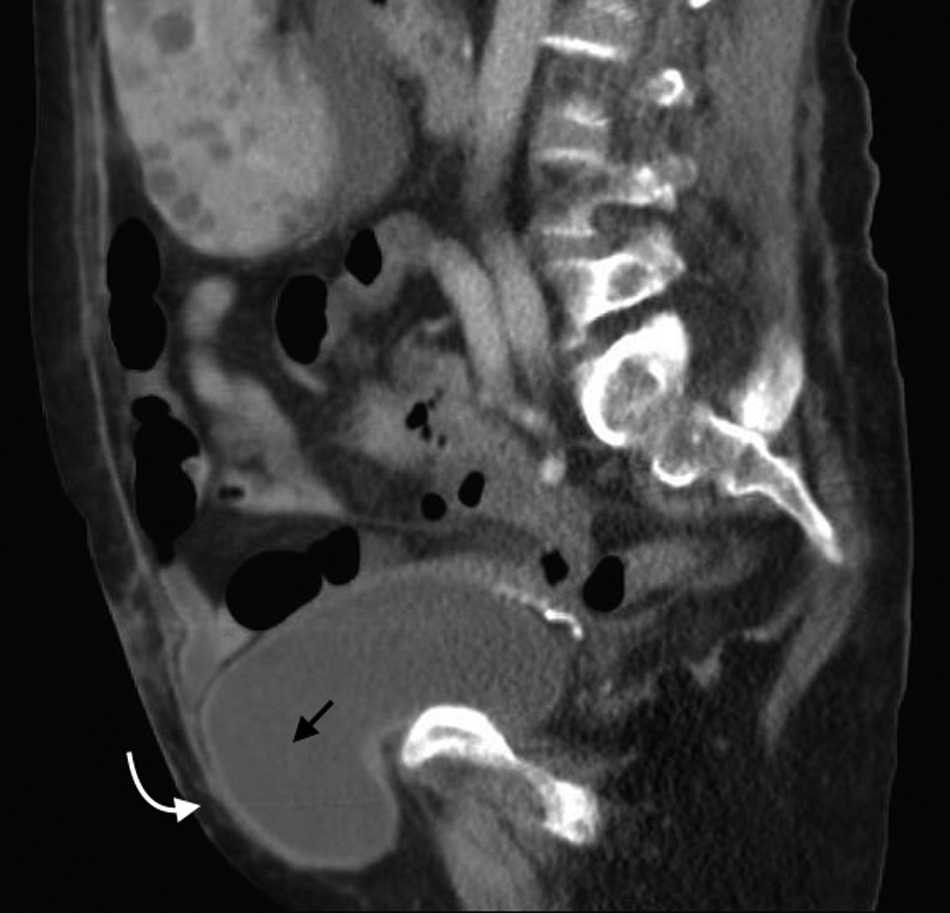

Puede producirse por puntos d??biles en la pared abdominal posterolateral4. Estos son: el tri??ngulo lumbar superior o de Grynfelt, limitado hacia arriba por la duod??cima costilla, hacia adentro por el m??sculo cuadrado lumbar, lateralmente por el m??sculo oblicuo interno y hacia atr??s por el m??sculo espinal; y el tri??ngulo inferior o de Petit, confinado por el m??sculo oblicuo externo en sentido anterior, el m??sculo dorsal ancho en sentido posterior y la cresta il??aca en sentido inferior2,13.

En su mayor??a estas hernias son adquiridas (espont??neas, postraum??ticas o posoperatorias). Las espont??neas representan aproximadamente el 50% de todas las de la zona lumbar y con mayor frecuencia ocurren en el tri??ngulo superior, con un contenido que puede ser de asas intestinales, grasa retroperitoneal o el ri????n14.

Los s??ntomas suelen ser variables y confusos. Algunas veces la consulta se debe a un dolor lumbar o a una neuralgia posincisional1 (fig. 7).

El contenido est?? relacionado con los diferentes sitios de debilidad de la pared. A nivel epig??strico se encuentra una herniaci??n del antro g??strico, del l??bulo hep??tico izquierdo (fig. 14) o de la ves??cula biliar (fig. 15). Por su parte, dentro de las umbilicales puede haber grasa peritoneal, asas intestinales, implantes metast??sicos (n??dulo de la hermana Mar??a Jos??) (fig. 16) o l??quido asc??tico (fig. 17). En la hernia de Spiegel suele visualizarse grasa y asas intestinales, mientras que las obturatrices muchas veces son descubiertas porque el paciente presenta un cuadro de obstrucci??n intestinal mec??nica que ayuda al diagn??stico. En cuanto a la lumbar, se puede herniar grasa, el polo renal o el l??bulo hep??tico derecho (fig. 18). En el caso de la inguinal, esta tiene un contenido muy variado, aunque la grasa peritoneal y las asas son los m??s frecuentes (fig. 19). Adem??s, puede herniar ??rganos intrapelvianos, como la vejiga (cistocele) (fig. 20) o el ap??ndice (hernia de Amyand)20 (fig. 21), y si se produce la herniaci??n del ap??ndice dentro del canal crural, se denomina hernia De Garengeot9 (fig. 22). Finalmente, en las eventraciones se observan asas de intestino delgado y grueso, ri??ones trasplantados (fig. 23) y vejigas (fig. 24).